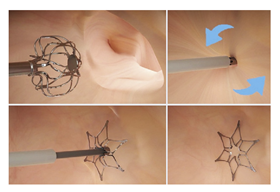

3.1. Surface Modification

| surface modification [104] | Advanced surface modification, using alternating nanoscale layers of TiN on NiTi alloy, enhancing endothelial cell migration and accelerating endothelialization; successful clinical implantation. | Lack of long-term studies on the effects and potential complications of the nanocoating in humans; limited clinical evidence, with only one reported case. |